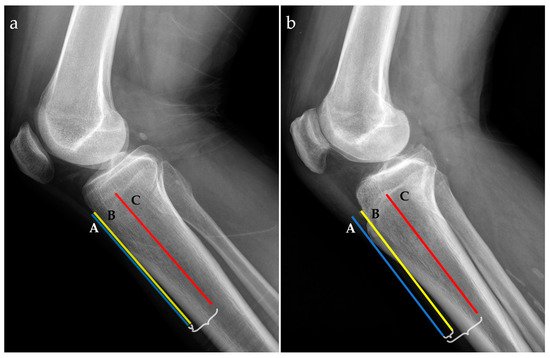

For radiographic examinations (Rx), the ATTI was obtained by the ratio of two distances; the first one measured between the anterior tibial cortex and a tangent line through the most prominent anterior point of the tibial tuberosity and the second one between the middle of the tibial diaphysis and a tangent line through the most prominent anterior point of the tibial tuberosity, as exemplified in Figure 2.

Figure 2.

Radiographic lateral views for two patients with low (a) and high (b) anterior tibial tuberosity index (ATTI). The following landmarks are represented: a tangent line at the most prominent point of the anterior tibial tuberosity (blue line, A), the anterior tibial cortex (yellow line, B), and the middle tibial diaphysis (red line, C). Distances between A and B, and A and C, respectively, are marked with accolades.